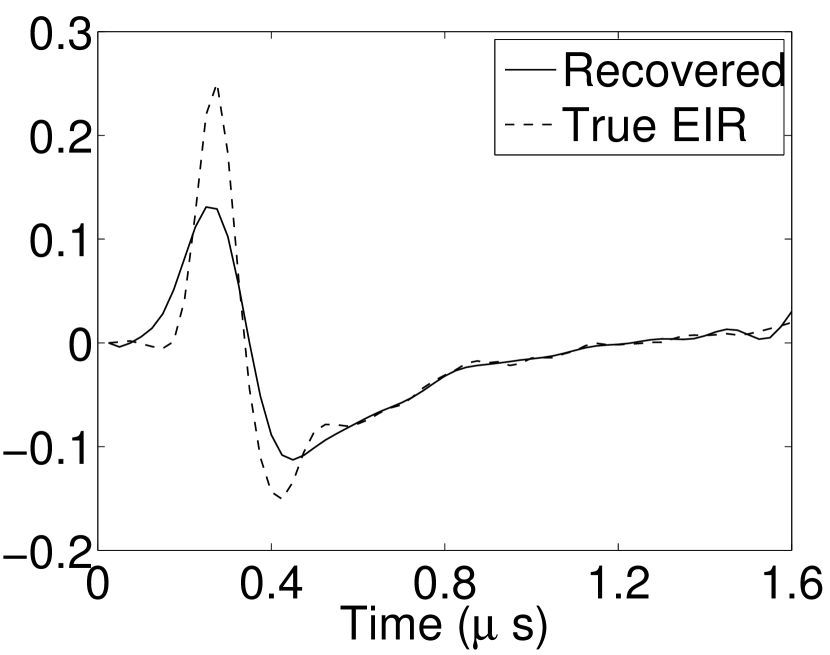

Figure 7(a) reveals that use of the inaccurate EIR in the conventional iterative method created strong artifacts and distortions. Figures 7(b) confirms that the artifacts and distortions were significantly mitigated when the VP method was employed. Image profiles for both cases are shown in Figures 7(c). The overall accuracy of the recovered EIR, shown in Figure 7(d) and 7(e), was improved, but it contained spurious oscillations.